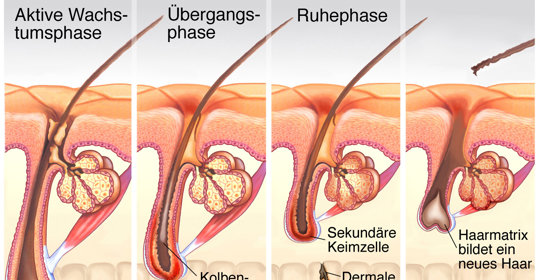

產後掉發的症狀、成因及預防方法大揭秘!

產後掉發是一種常見的生理現象,但給女性造成困擾。本文大揭秘了產後掉發的症狀、成因,並提供了實用的預防方法,包括合理的飲食、注意頭皮護理等,幫助產婦有效減輕產後掉發的問題。